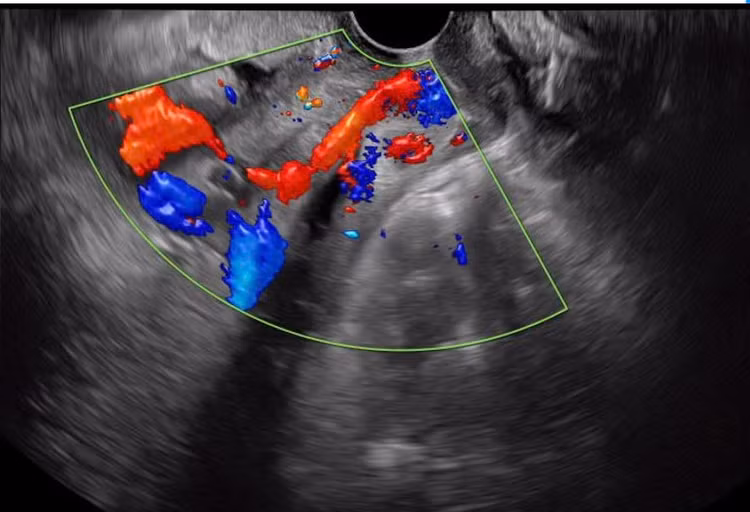

| Rau tiền đạo, mạch máu tiền đạo - Ảnh BVCC |

Mạch máu tiền đạo có thể được chẩn đoán bằng cách siêu âm đầu dò kết hợp với siêu âm Doppler. Bác sĩ khuyến nghị thực hiện siêu âm mạch máu tiền đạo cho các thai phụ có nguy cơ cao đặc biệt các bà mẹ được chẩn đoán có nhau cài răng lược hoặc có các dấu hiệu cảnh báo mắc phải hiện tượng này.